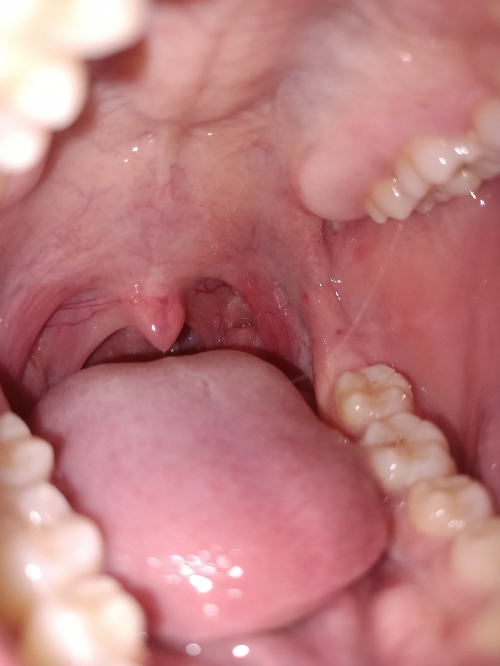

Họng e có hơi viêm 1 chút